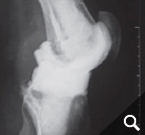

In order to diagnose these infections, tissue samples are taken from the joint in addition to a puncture, as only close cooperation between orthopedists, pathologists and microbiologists can ensure the correct diagnosis. In addition, we also devote ourselves to obviously infected prostheses, of course. These infections can occur shortly after the operation (so-called early infection up to 6 weeks postoperatively) but also years after the operation (as so-called late infection). In addition to the smallest entry points (e.g. an ulcerated toenail), serious infections such as pneumonia can also lead to bacteria colonizing the surface of the prosthesis. Patients with a limited immune system (e.g. diabetics, rheumatics) are particularly at risk. If an infection is noticed early enough after surgery, it is occasionally still possible to eliminate the infection without removing the prosthesis by carefully cleaning the wound and changing the moving parts.

However, infections often go unnoticed for many weeks, so that removal of the prosthesis is unavoidable. Depending on the pathogen and its sensitivity, a placeholder containing antibiotics is then implanted, which remains in place for 6 weeks. Antibiotics in tablet form must then also be taken for this period. However, it is not necessary for a patient to remain in the hospital during this entire period. If home care is not possible, for example, it is also possible to organize this in close cooperation with our social services. After 6 weeks it is generally possible to reimplant a prosthesis, provided that the blood values show that the infection is under control. Antibiotics must then be taken again for 6 weeks after surgery. Which antibiotics are taken is determined in close cooperation with colleagues in microbiology and clinical pharmacology, with whom regular rounds and therapy checks are carried out. These therapeutic measures are carried out in a special area of the clinic using the most modern methods.